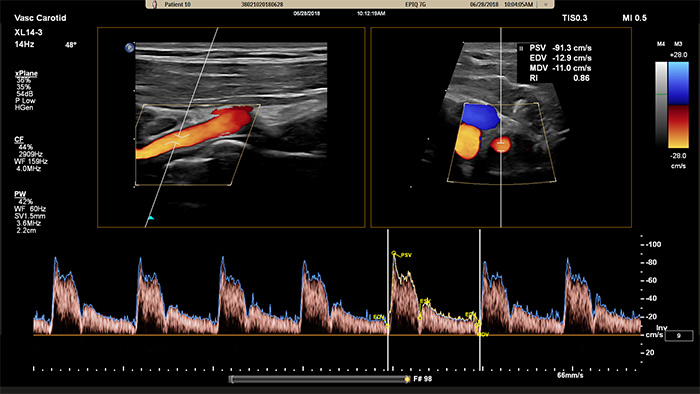

XL14-3 xMATRIXは、xPlaneドプラ機能も備えています。xPlaneパルスドプラは縦断面および横断面の参照画像を使用して、ドプラサンプルボリュームの位置決めを正確に行います。xPlaneドプラの主なメリットには、有意狭窄のサンプリング時に、サンプルボリュームの位置決めエラーを減少させ、高い再現性と一貫性を実現する点が挙げられます。